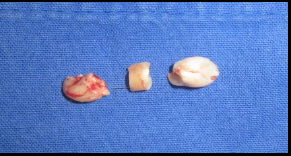

Por la ubicación del diente, se decide realizar el procedimiento bajo anestesia general, por lo que se coloca adicionalmente lidocaína con epinefrina local para vasoconstricción. Se procede a realizar un colgajo semilunar cercano al fondo de saco vestibular superior. Se contornea la pieza dentaria y se realiza odontosección horizontal para retirar en tres segmentos (figura 4). Se realizó una valoración para revisar el defecto dejado por el canino y no se observó una comunicación directa con seno maxilar, por lo que no se adicionaron materiales para separar cavidades. Se cierra el colgajo y se termina la intervención quirúrgica sin complicaciones. Se tomó una radiografía final (figura 5).